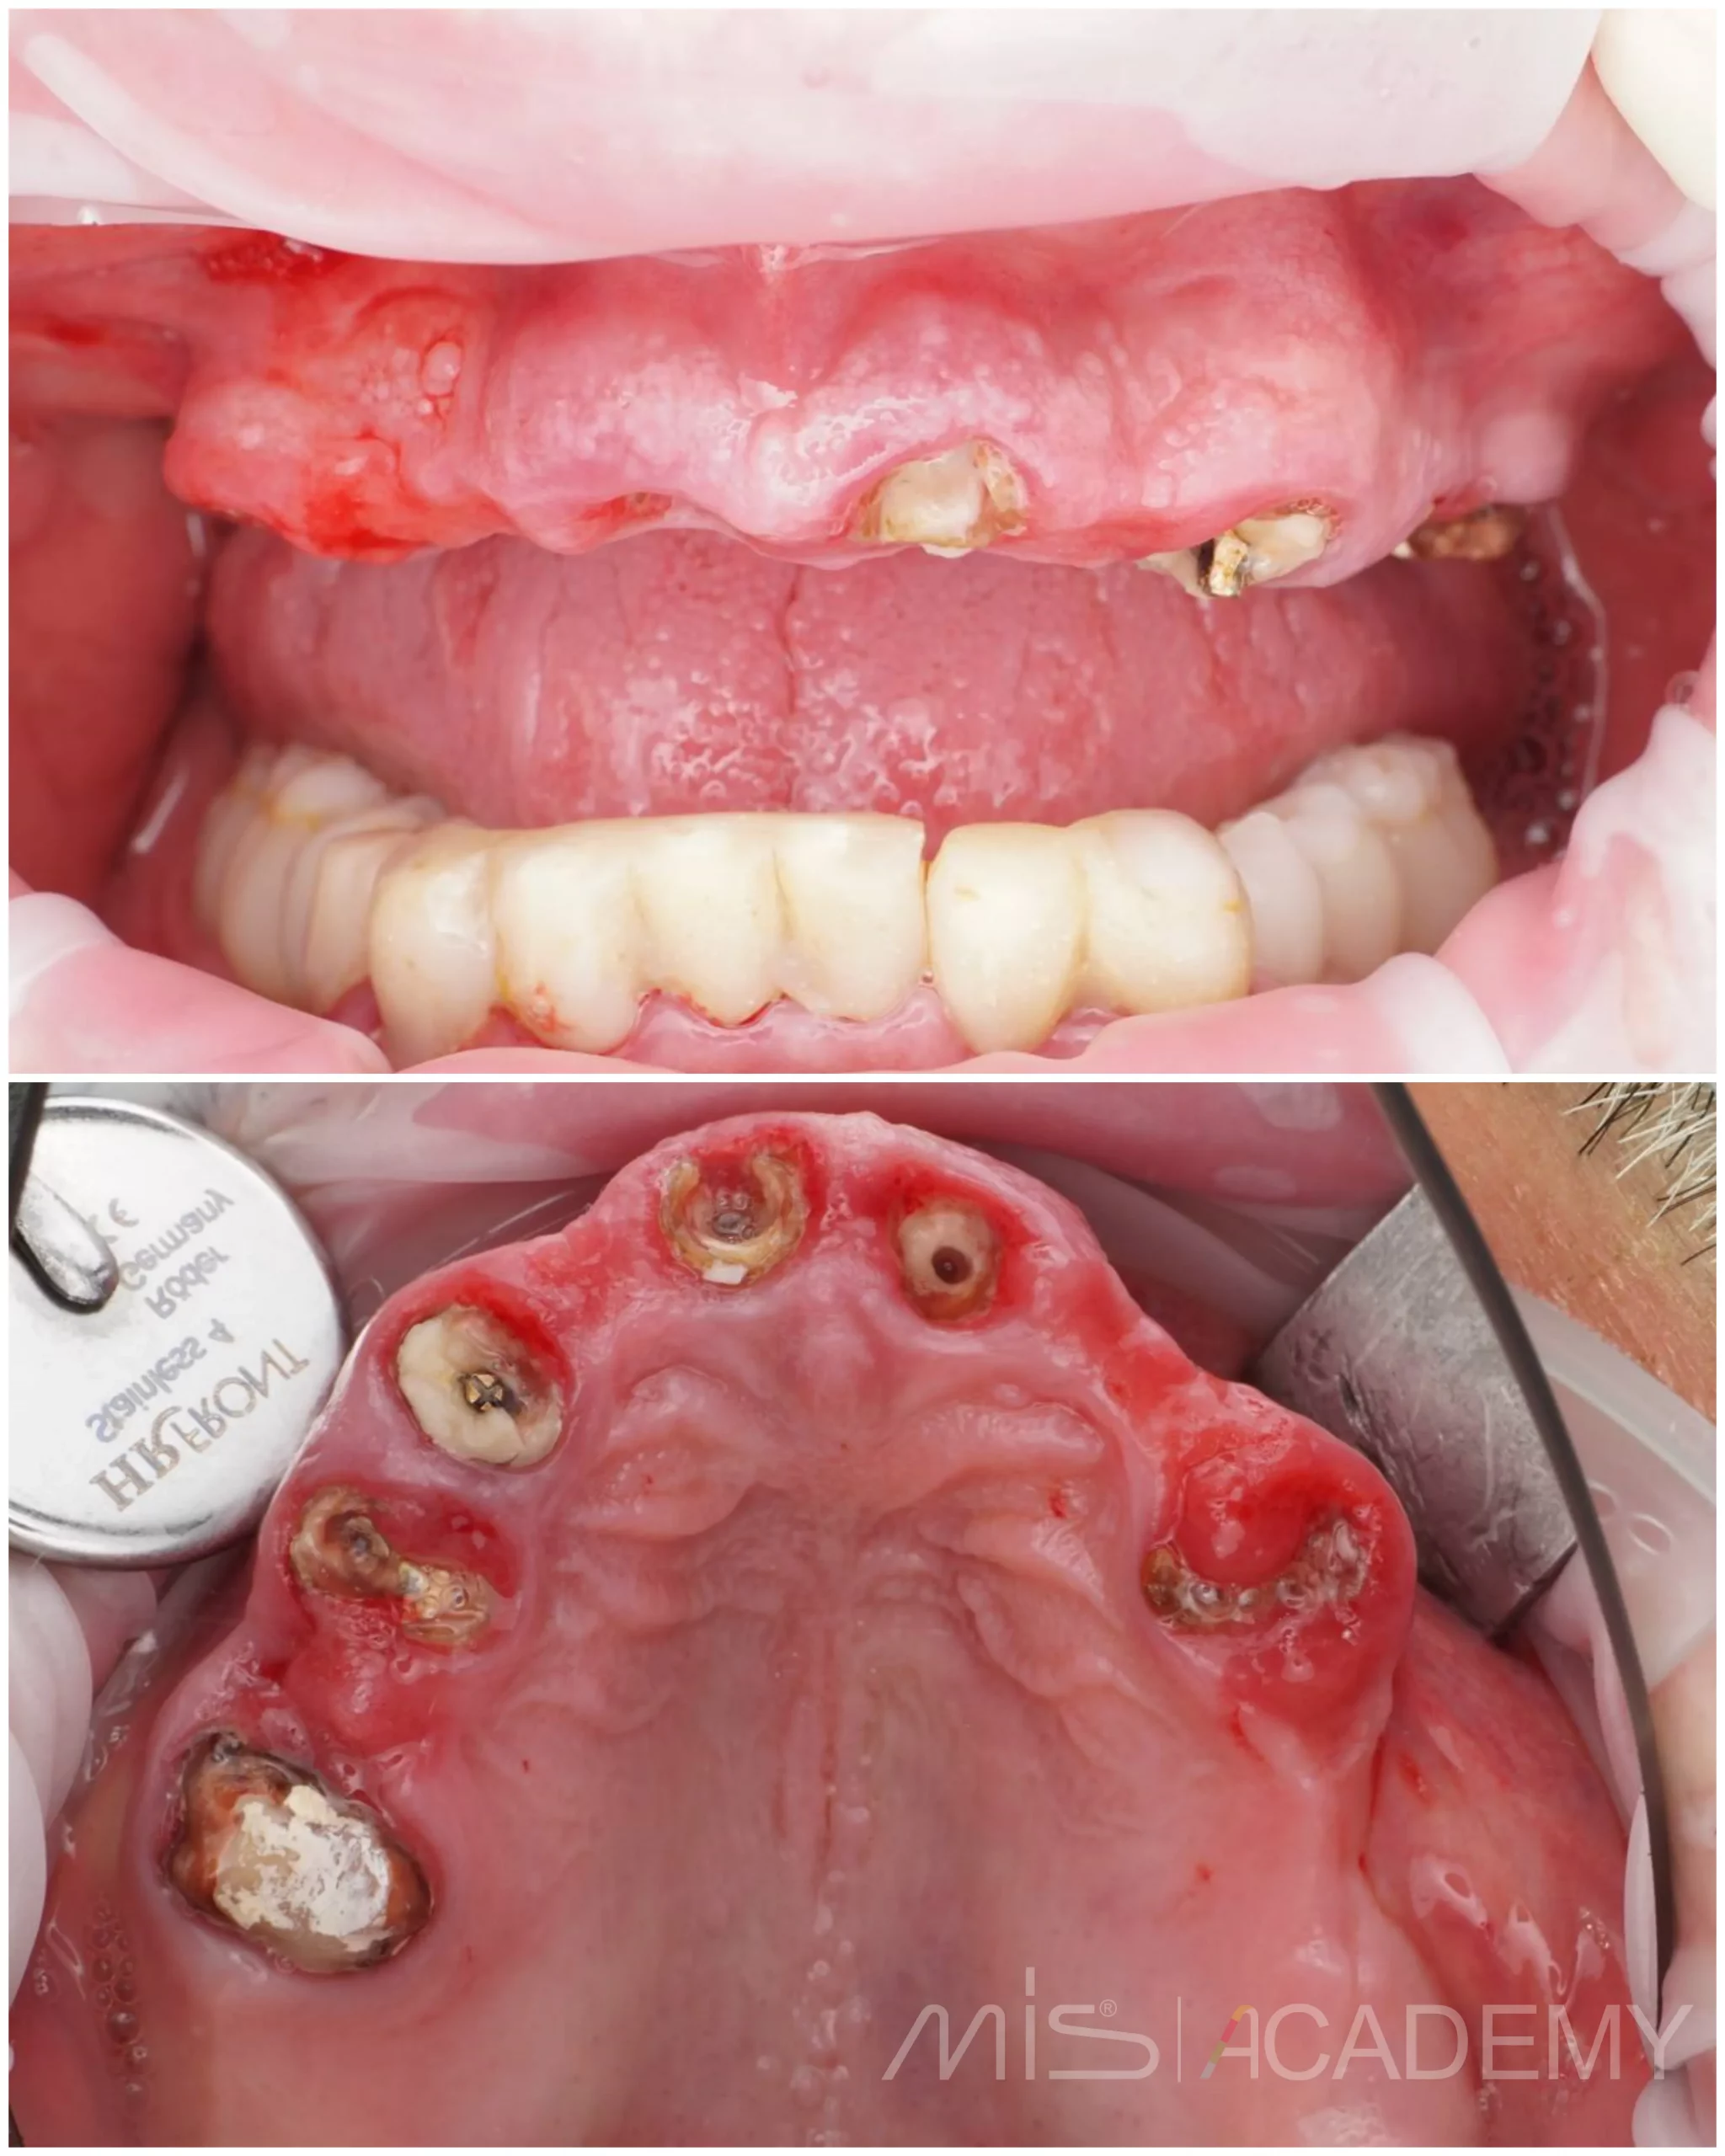

В подобных случаях мы планируем накостные, либо гибридные шаблоны и преимущественно из металла.

— Удаление всех несостоятельных зубов на верхней челюсти.

— Установлены имплантаты Mis C1 и два открытых синус лифтинга в дистальных отделах.